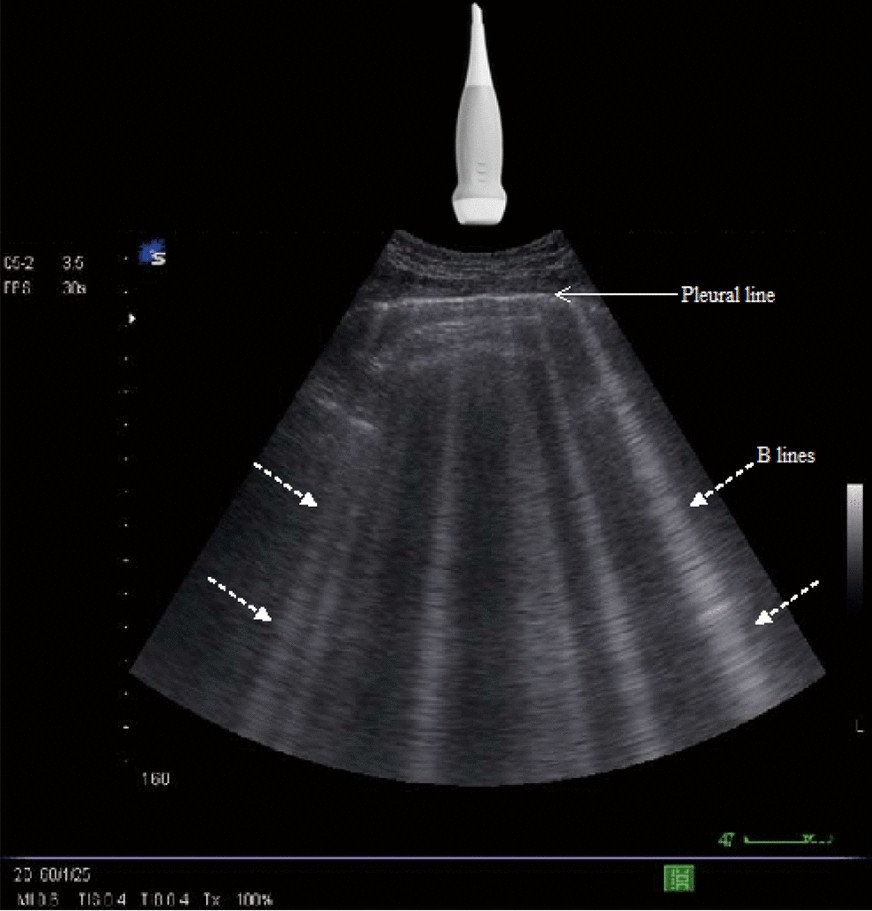

Edema: ≥3 B-lines per hpf bilaterally → Interstitial edema

Q18: What defines interstitial edema on lung ultrasound?

A18: ≥ 3 B-lines per hpf bilaterally